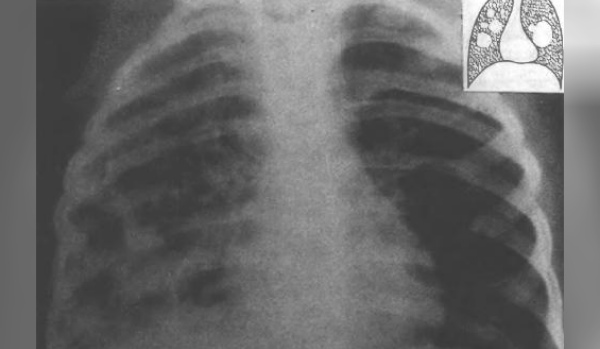

Бактериальная деструкция легких у детей презентация - 88 фото